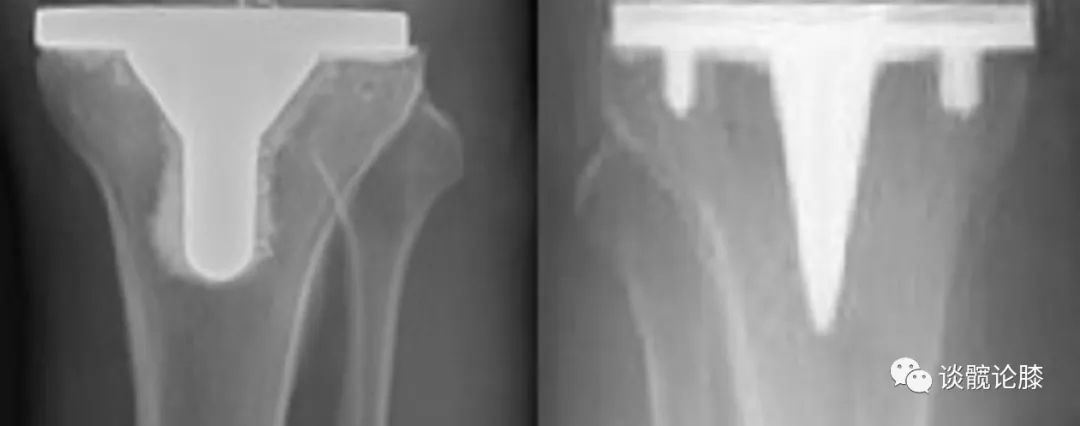

骨水泥按涂抹范围分

1、全层骨水泥技术(左图):平台下方及中心杆周围均涂抹骨水泥2、表面骨水泥技术(右图):仅在平台下方均涂抹骨水泥(研究显示:PS假体,两种疗效相似;CR假体,表面骨水泥技术松动率高)

有限元分析:表面骨水泥技术术后,胫骨近端应力遮挡小生物力学:表面骨水泥技术,术后假体稳定性较差